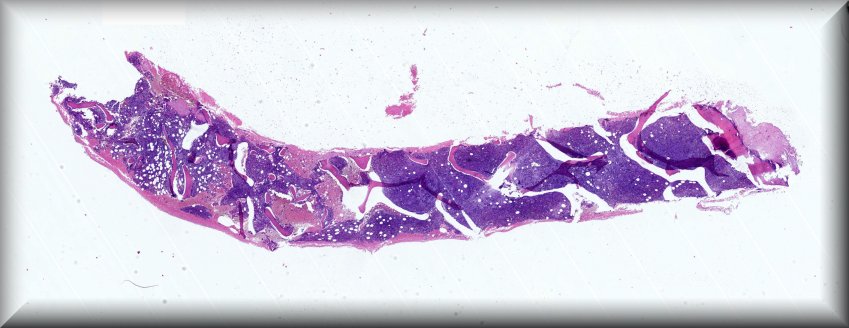

Caso 3.- Irene Salazar Saura, Josep Marí Alexandre, Sara Alemán Sánchez, Jose Joaquín Llopis Linares, Lara Navarro Cerveró, Esther Roselló Sastre.

Hospital General Universitario de Valencia.

Varón de 16 años con historia de un mes de evolución de astenia y palidez cutánea, que presenta cuadro adenopático inguinal y sospecha de trombosis venosa profunda, con síndrome leucoeritroblástico en sangre periférica.